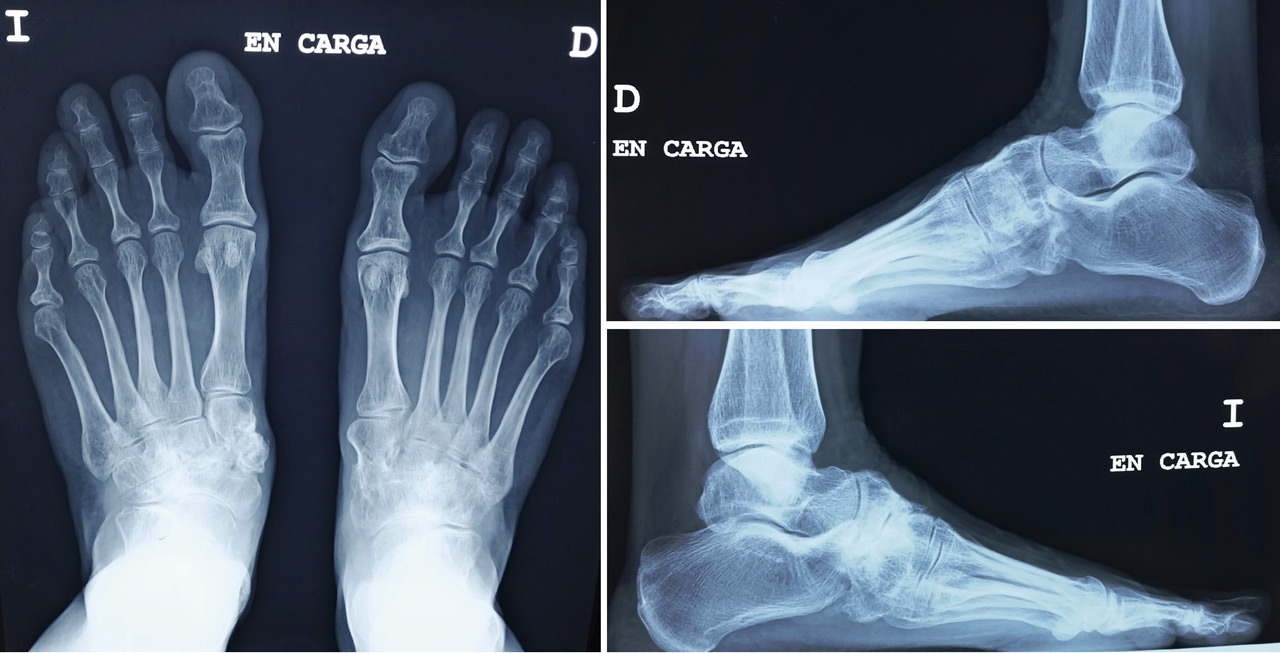

En el estudio mediante radiología simple en carga (Figura 2) se aprecia en la proyección dorsoplantar una desestructuración en la primera cuña con fragmentación y desplazamiento medial del fragmento proximal, así como cambios degenerativos escafocuneanos e intercuneanos. En la proyección lateral vemos un hundimiento de la columna medial a nivel transcuneano. En ambas proyecciones se aprecia una buena consolidación en el pie contralateral (clínicamente asintomático).

Figura 2. Radiografía preoperatoria.